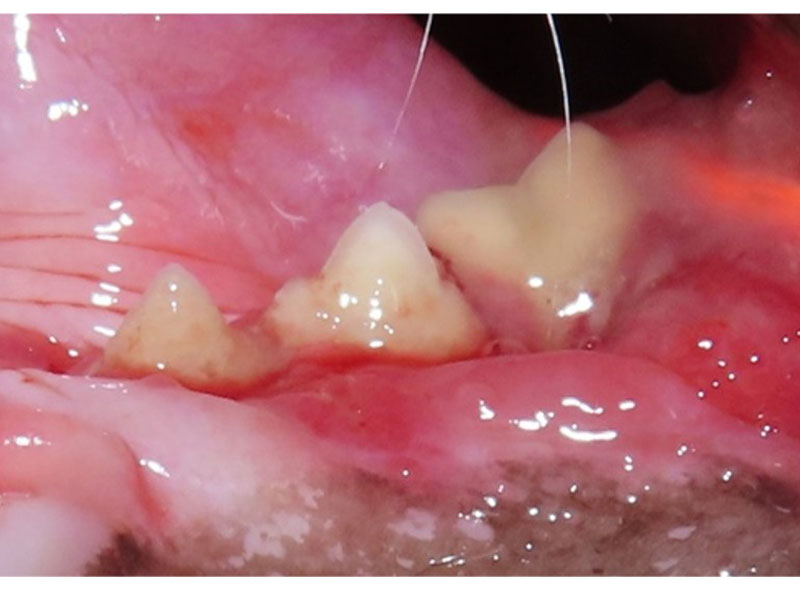

犬の吸収病巣

歯頚部が溶けています。

歯髄まで侵されると痛みを感じるため、噛むときに使わなかったり、歯磨きを嫌がるようになります。